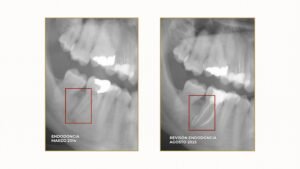

Endodoncia de calidad: Revisión tras 11 años

En Aparicio Laguna no buscamos soluciones rápidas, sino resultados seguros, predecibles y que cuiden de tu sonrisa durante muchos años. Hoy os presentamos un...